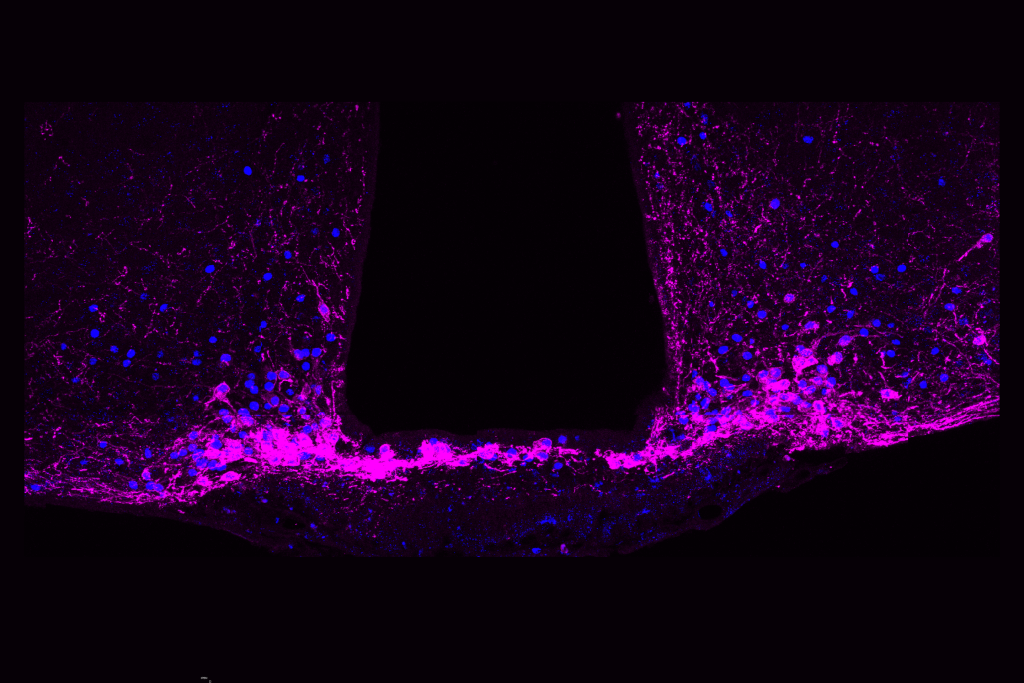

श्वान (Schwann) कोशिकाएं मस्तिष्क के बाहर परिधीय तंत्रिका तंत्र (peripheral nervous system) में पाई जाती हैं और माइग्रेन (migraine pain) तथा अन्य प्रकार के दर्द का कारण होती हैं। फ्लोरेंस विश्वविद्यालय (University of Florence) के पियरेंजेलो गेपेटी ने श्वान कोशिकाओं में एक किस्म के प्रोस्टाग्लैंडिन (PGE2) पर ध्यान केंद्रित किया, जिसे शोथ सम्बंधी दर्द (inflammatory pain) का एक मुख्य मध्यस्थ माना जाता है।

कोशिका झिल्लियों पर PGE2 (PGE2 receptors) के लिए चार अलग-अलग रिसेप्टर्स होते हैं। गेपेटी के पूर्व अध्ययनों ने PGE2 के लिए EP4 रिसेप्टर (EP4 receptor) को शोथ सम्बंधी दर्द उत्पन्न करने वाले मुख्य रिसेप्टर के रूप में इंगित किया है। हालांकि, नेचर कम्युनिकेशंस (Nature Communications research) में, शोधकर्ताओं ने एकाधिक लक्ष्य आधारित दृष्टिकोण अपनाया और पाया कि एक अलग रिसेप्टर (EP2) दर्द के लिए काफी हद तक ज़िम्मेदार था। श्वान कोशिकाओं में केवल EP2 रिसेप्टर को शांत करने के लिए स्थानीय रूप से दवाइयां देने पर चूहों में शोथ को प्रभावित किए बिना दर्द प्रतिक्रियाएं दूर हो गईं। इस प्रकार शोथ को दर्द से प्रभावी रूप से अलग कर दिया गया। यह शोध दर्द निवारण (pain relief research) के क्षेत्र में एक नई दिशा देता है। (स्रोत फीचर्स)